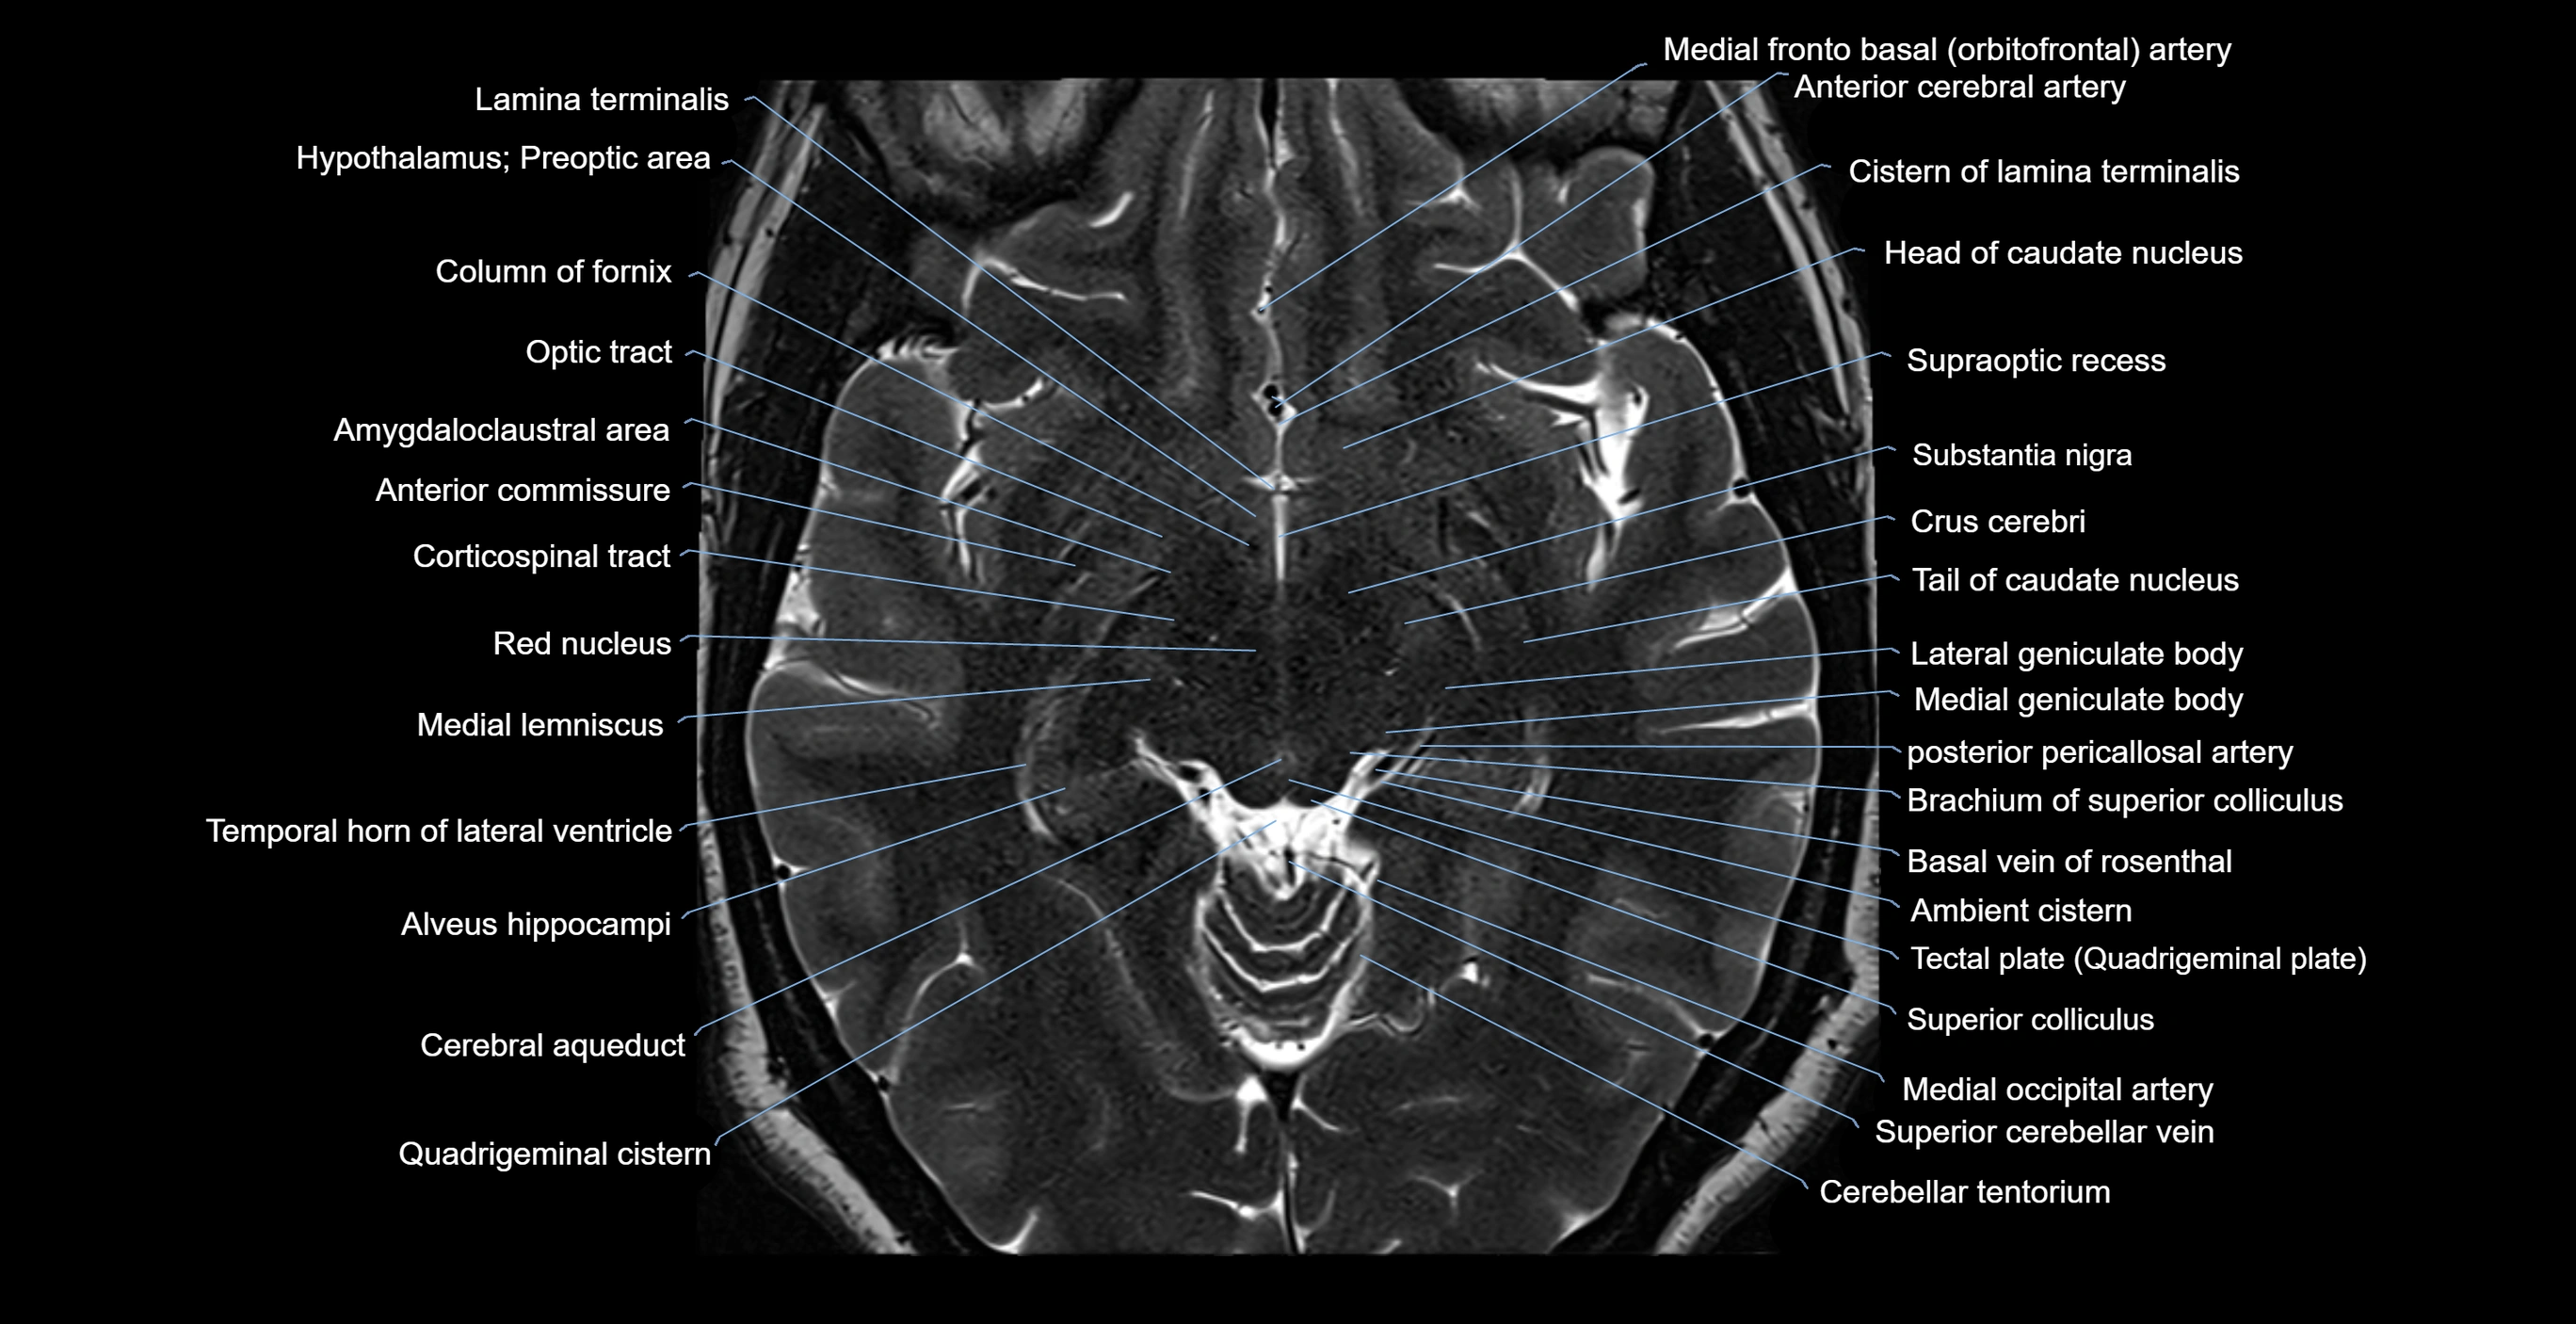

MRI images